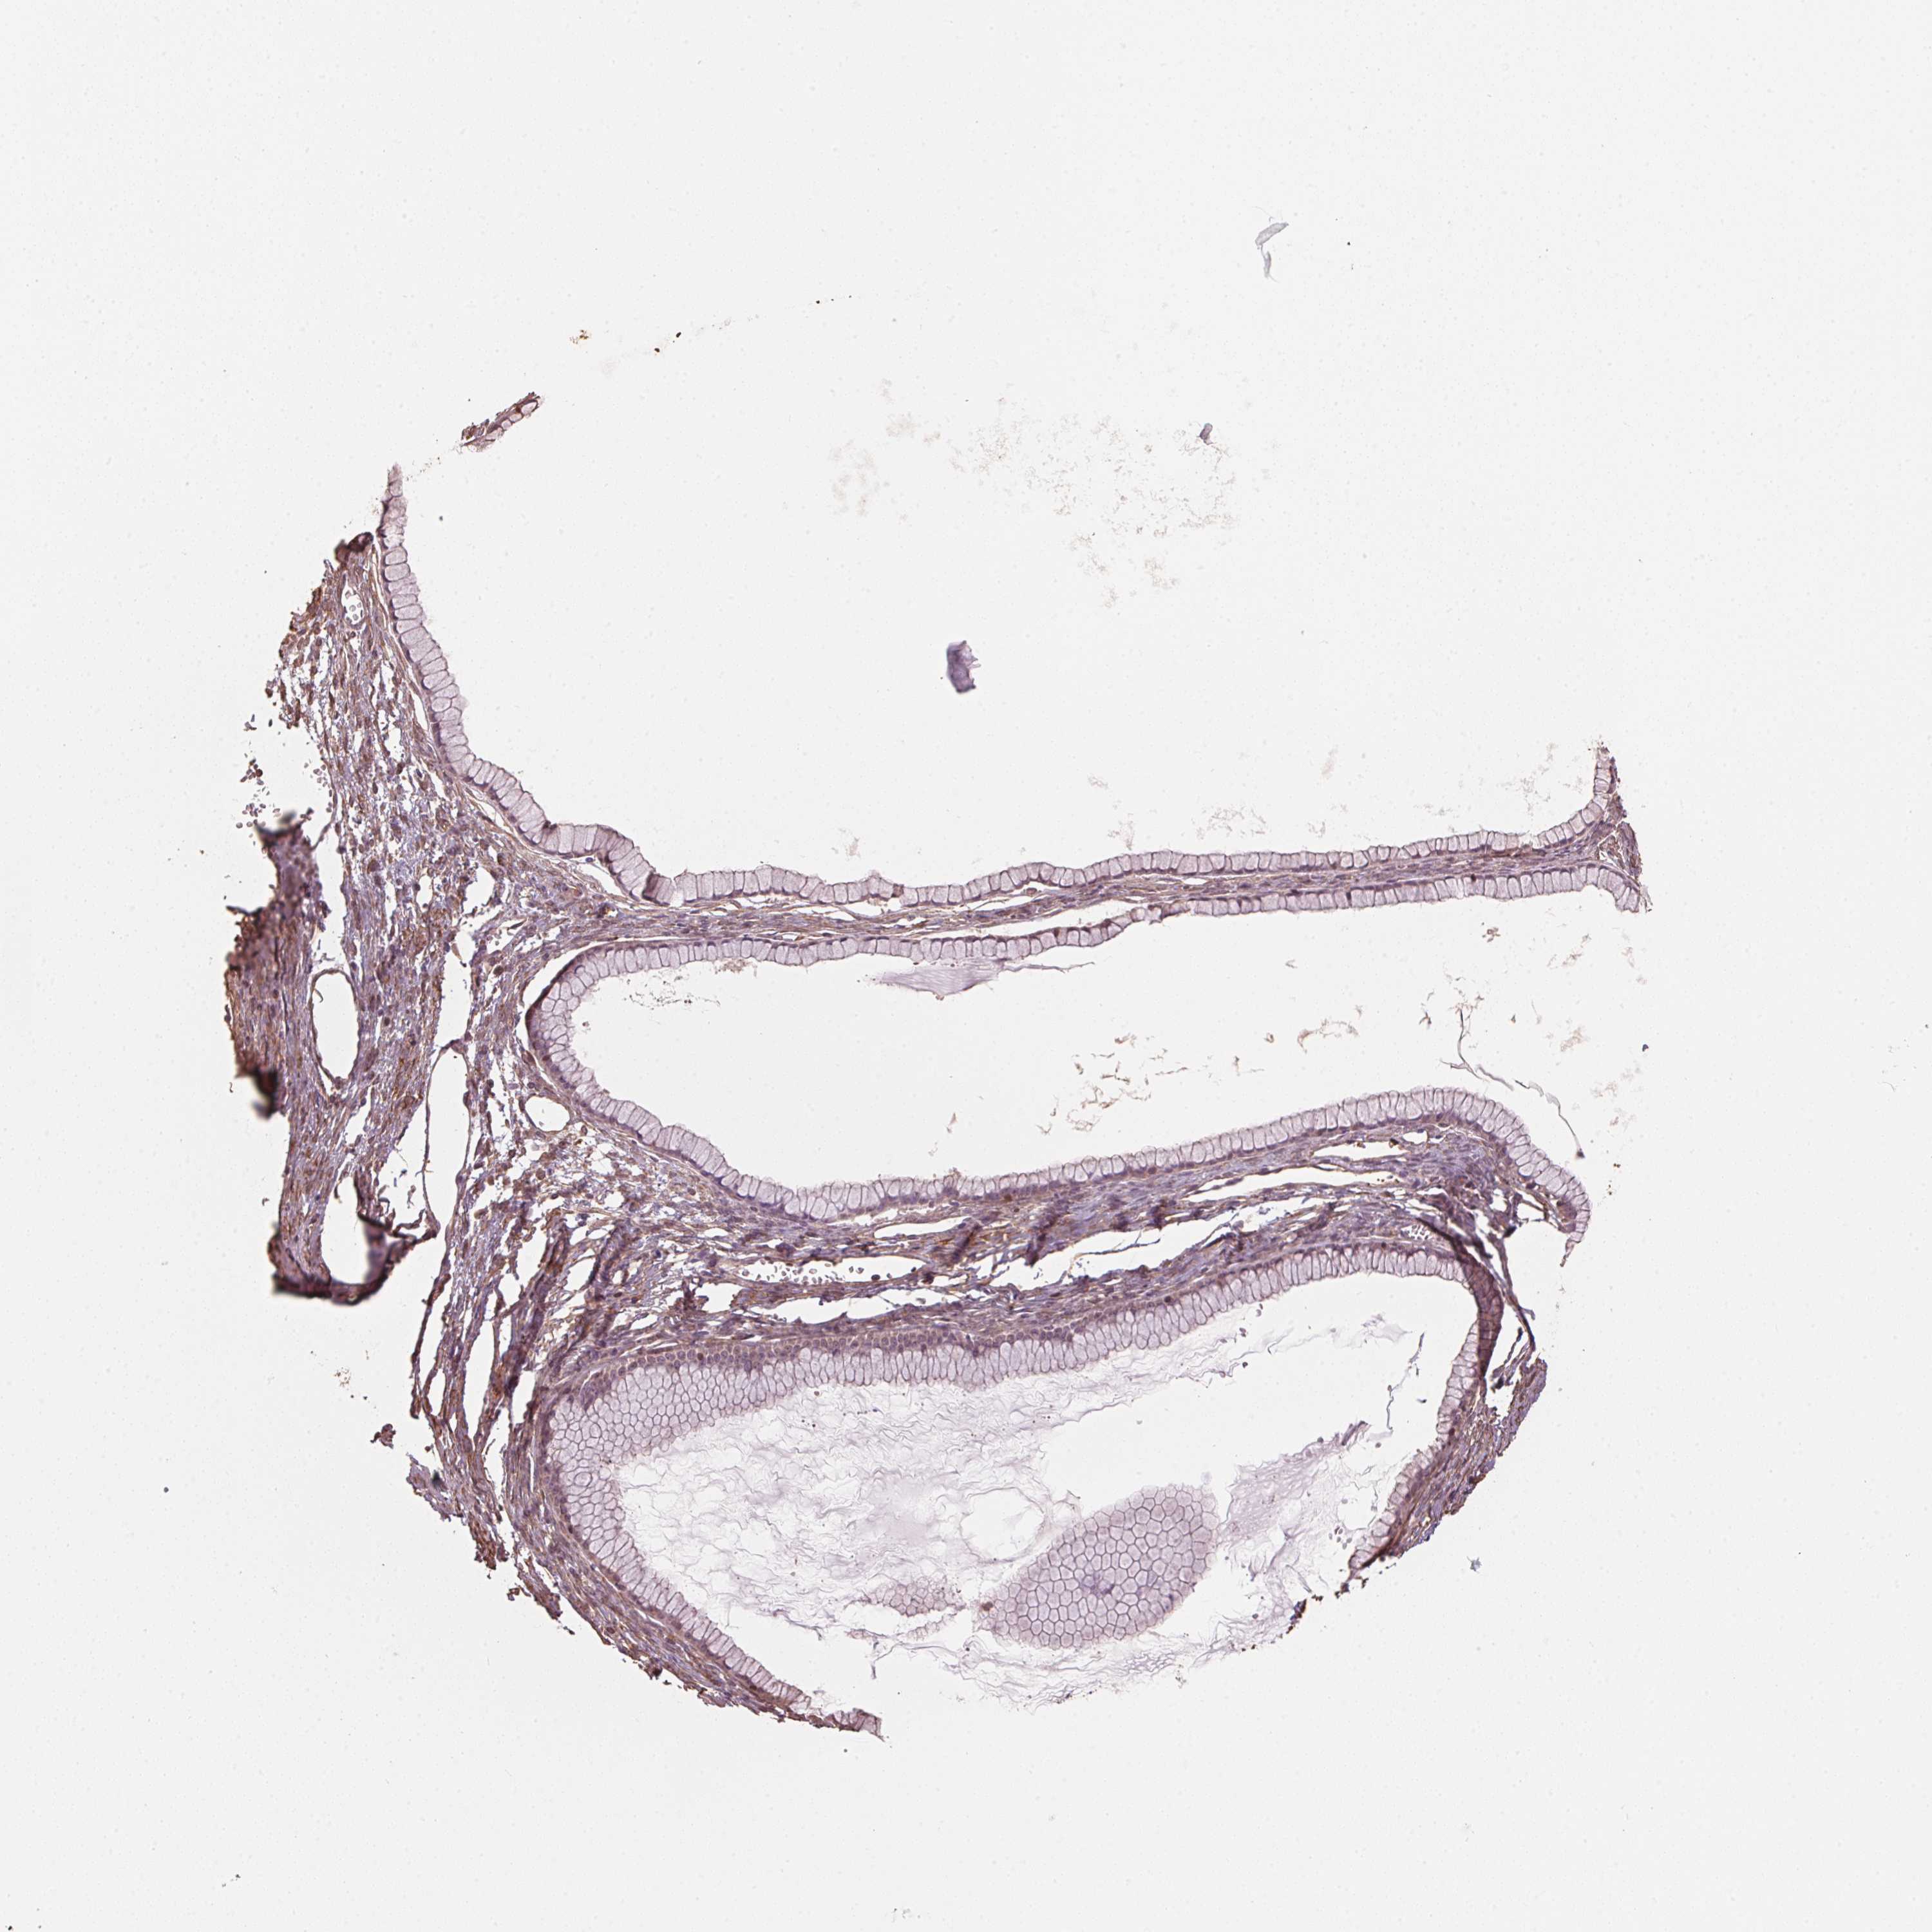

OVARIAN CANCER - Protein expressioni

A mouse-over function shows sample information and annotation data. Click on an image to view it in a full screen mode. Samples can be filtered based on level of antibody staining by selecting one or several of the following categories: high, medium, low and not detected. The assay and annotation is described here.

Note that samples used for immunohistochemistry by the Human Protein Atlas do not correspond to samples in the TCGA dataset.

Antibody stainingi

Antibody staining in the annotated cell types in the current human tissue is reported as not detected, low, medium, or high, based on conventional immunohistochemistry profiling in selected tissues. This score is based on the combination of the staining intensity and fraction of stained cells.

Each image is clickable and will lead to virtual microscopy that enables deeper exploration of all samples and also displays staining intensity scores, fraction scores and subcellular localization as well as patient and tissue information for each sample.

Antibody HPA065649

Cystadenocarcinoma, mucinous, NOS

Carcinoma, endometroid

Cystadenocarcinoma, serous, NOS